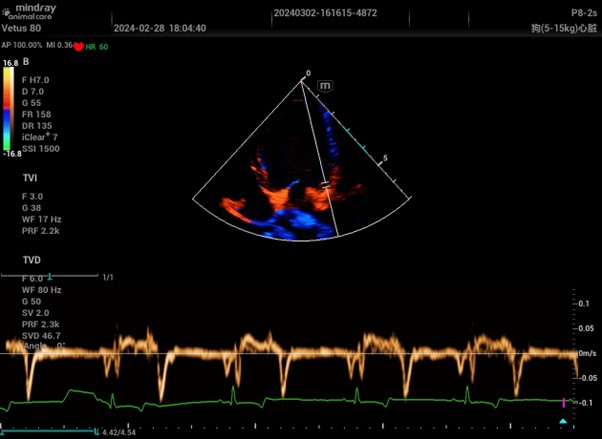

Colour and Pulsed Wave Tissue Doppler Imaging from a Mindray Vetus 80

This mode is used in specialist echocardiography, often called Tissue Velocity Imaging (TVI) or Tissue Doppler Imaging (TDI). There are two types, colour and pulsed wave. They are simply more specialised versions of their namesakes above, optimised for tissue movement rather than blood flow.